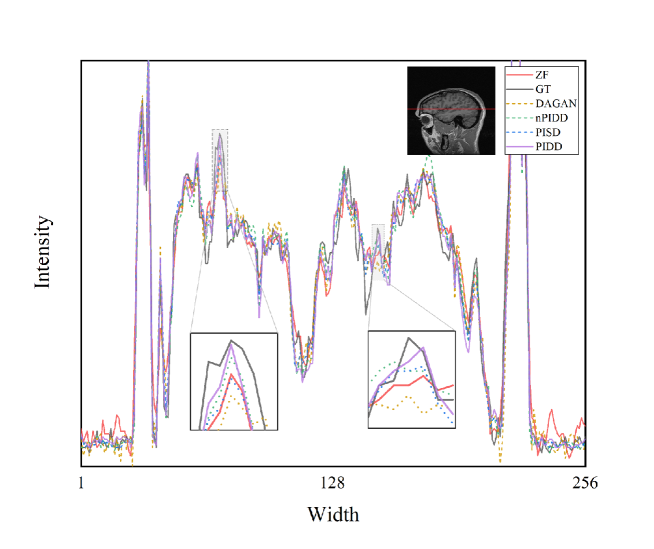

Horizontal line profiles of the samples in Fig. 5 are shown in Fig. 6. ZF and DAGAN still contain lots of noise, while our proposed methods preserve more detail information. Zoom-in areas clearly show that the line profile of PIDD-GAN achieve more accurate than other methods.